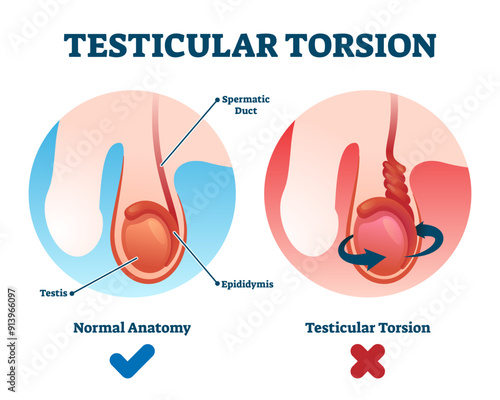

Testicular - Posters, Quadros em tela